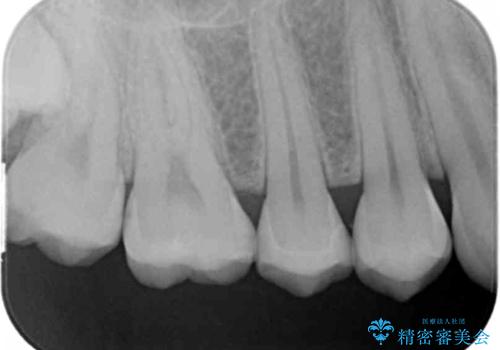

- 健診にて来院。

症状はないものの奥歯に黒ずんだ箇所があるため治療を進めていくことになりました。

外からも確認できる虫歯だけでなく、歯の奥の面の虫歯も残さず除去しました。

残った歯の量が多かったためインレータイプでの修復となりました。